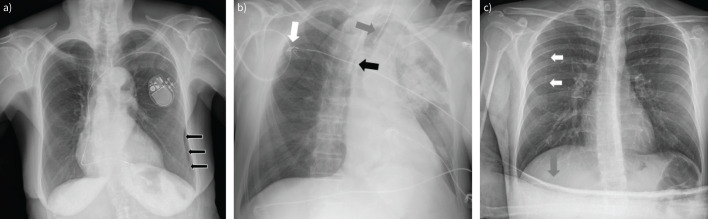

Imaging methods are fundamental tools to detect and diagnose lung diseases, monitor their treatment and detect possible complications. Each modality, starting from classical chest radiographs and computed tomography, as well as the ever more popular and easily available thoracic ultrasound, magnetic resonance imaging and nuclear medicine methods, and new techniques such as photon counting computed tomography, radiomics and application of artificial intelligence, has its strong and weak points, which we should be familiar with to properly choose between the methods and interpret their results. In this review, we present the indications, strengths and main limitations of methods for chest imaging.